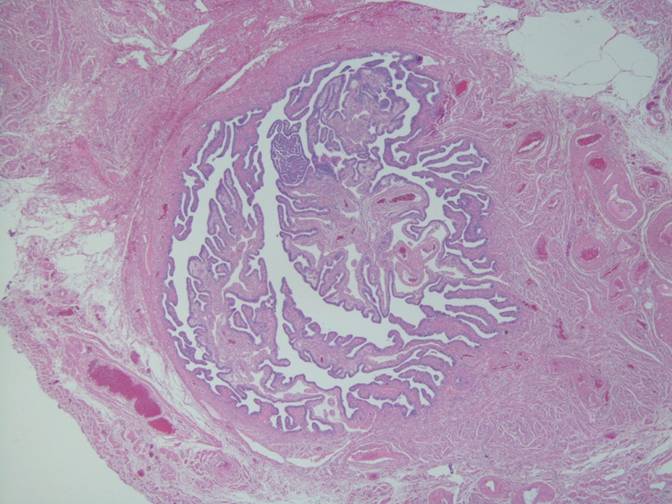

子宮膣部細胞診に出現した卵巣漿液性腺癌のの一例

- 子宮膣部